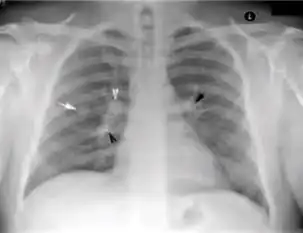

2. Any cavitary lesion - Lucency (darkened area) within the lung parenchyma, with or without irregular margins that might be surrounded by an area of airspace consolidation or infiltrates, or by nodular or fibrotic (reticular) densities, or both. The walls surrounding the lucent area can be thick or thin. Calcification can exist around a cavity.

Chest X-ray of a person with advanced tuberculosis: Infection in both lungs is marked by white arrow-heads, and the formation of a cavity is marked by black arrows.